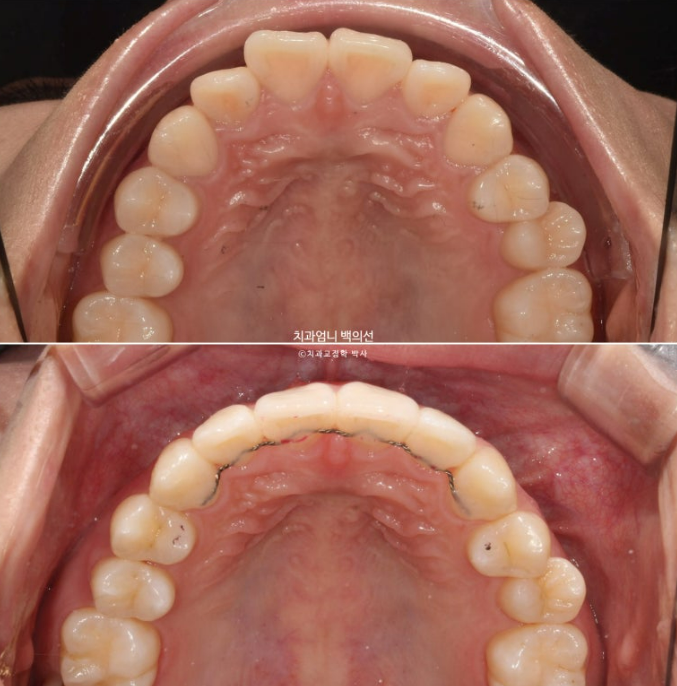

23년 12월 앞니 부분교정을 위해 오신 분입니다.

앞니 두 개가 크기도 하고 내려와 있습니다.

파란 화살표에 작은 어금니 덧니도 보입니다.

아래 앞니가 많이 삐뚭니다.

어금니 교합이 그리 좋은 편은 아니지만 환자분은 씹는데 불편함을 못 느끼는 상태였고 앞니 배열만 원하셨습니다.

치료시작 9개읠째 모습입니다.

앞니 사이 미세한 틈을 없애기 위해 파워체인 고무를 걸고

사진에 보이는 고리끼리는 환자분이 스스로 뺐다 꼈다 하는 고무줄을 걸고 중심선과 좌우 교합까지 마춥니다.

그러다보니 어느덧 9개월이 흘렀습니다.

MTA 장치는 송곳니부터 송곳니까지 앞니에만 붙여서 배열을 진행했고 나머지 작은어금니와 큰어금니는 움직이지 않았습니다

24년 9월 드디어 치료가 마무리되었습니다.

24.09

유지장치까지 붙은 모습입니다. 총 치료기간은 9개월입니다.